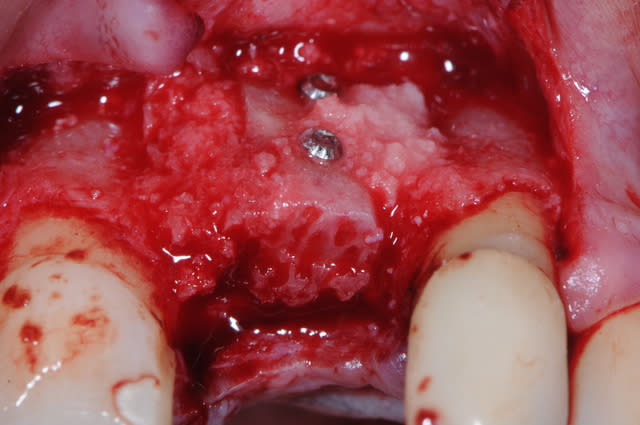

voici un petit cas de greffe sur une zone antérieur.

le patient est édenté de 21 depuis plusieurs mois, donc plus d'os en vestibulaire.

1 :préparartion du lit par un prélèvement avec tréphine

2-3-4 :lit receveur

1-2 : vis d'ostéosynthèse Stoma ; diamètre 1 mm (ceux sont les plus petites du marché)

3 vérification de l'adaptation du greffon au lit receveur

(au moins avec cette technique on a pas beaucoup de travail de préparation...)

4 stabilisation pince stoma

5 greffon en place

6 broyats osseux :mélange d'autogène et du reste du bloc

7-8: hiatus comblés

9 : A-PRF

10 : sutures glycolon 6/0 sans tension

pour les greffes, je m'oblige à mettre du fil très fin pour ne pas être tenté de tirer sur le lambeau.